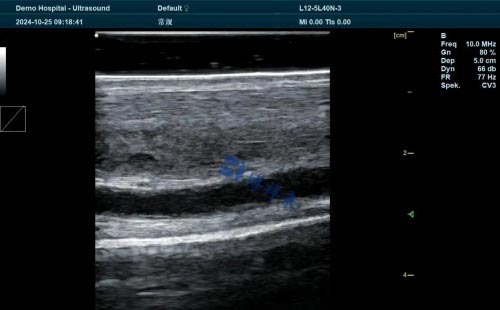

Look for systems that support multiple probe types—linear, convex, and micro-convex. The ability to switch probes makes the device more versatile across different applications such as pregnancy checks, abdominal exams, or musculoskeletal assessments.Image Quality and Depth Penetration

Cows and horses have thick body walls, so image penetration depth is crucial. Machines should offer a penetration of at least 20–30 cm with adjustable frequency settings to balance resolution and depth as needed.Rugged Design and Waterproofing